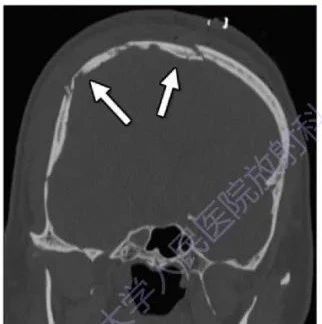

脑外伤及其并发症影像诊断

脑外伤及其并发症影像表现